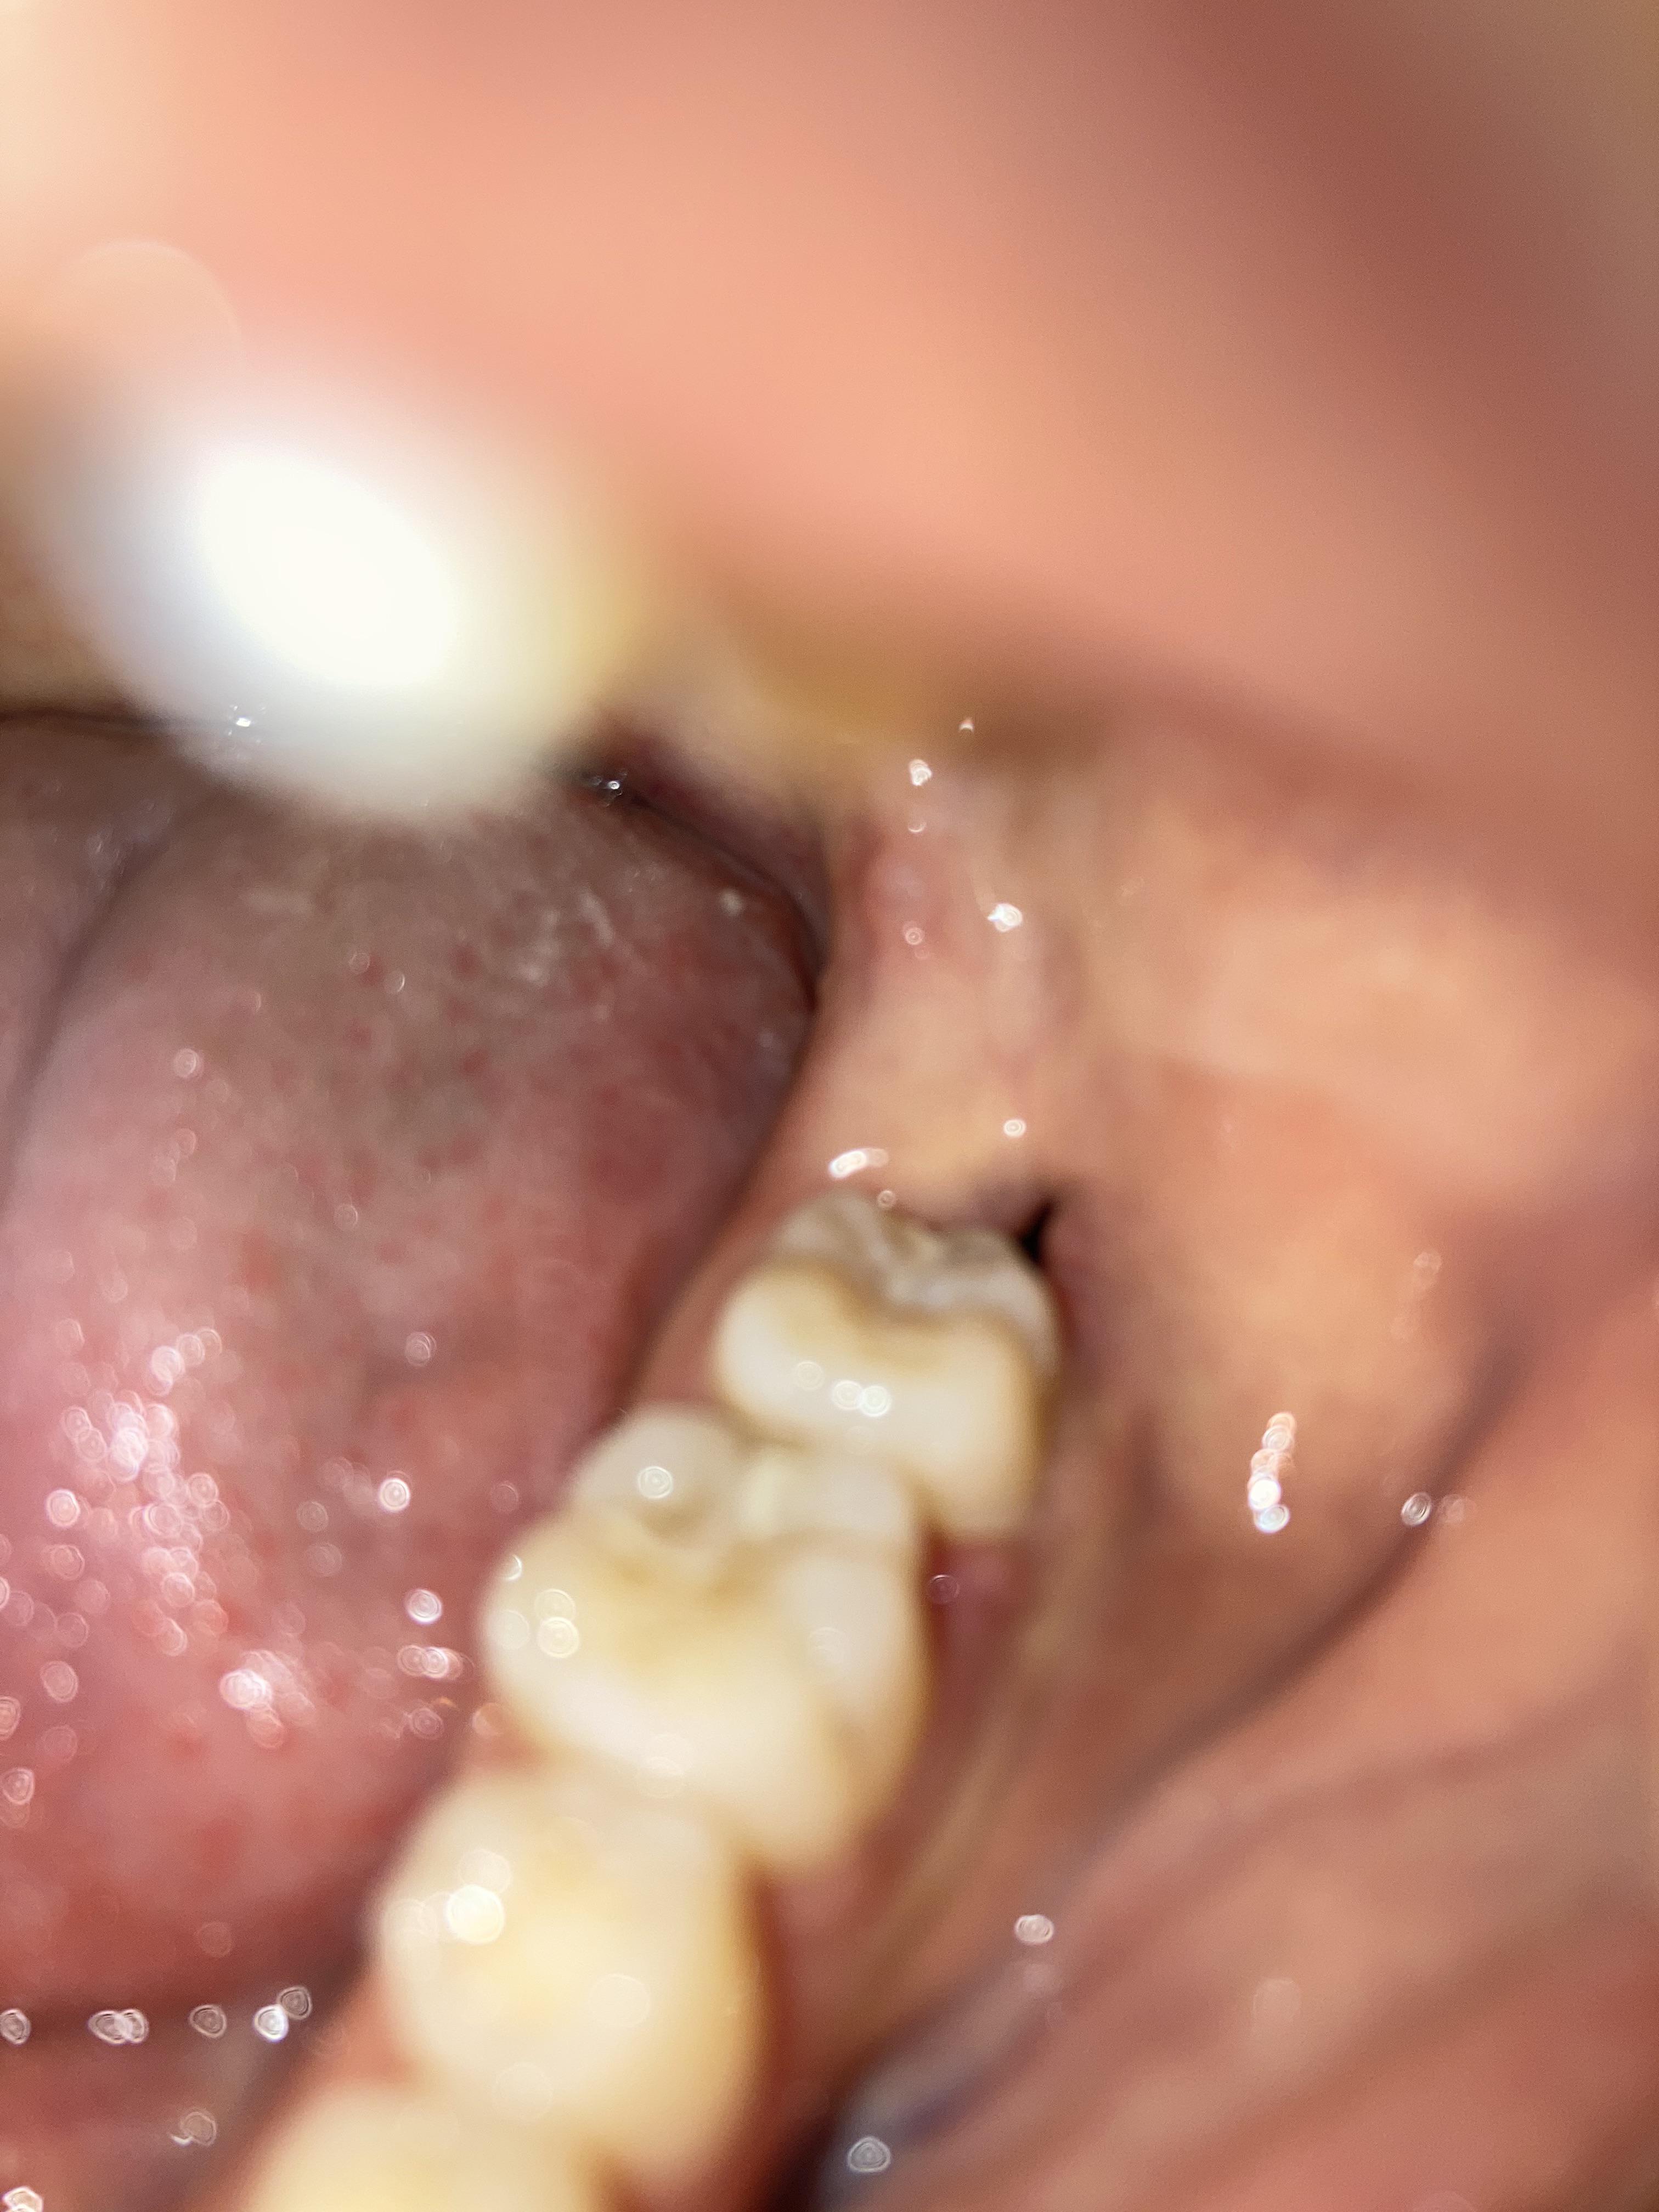

I had all 4 of my impacted teeth removed 9 days ago. The dissolvable stitches on my lower left Dental Dissolvable Stitches Not Dissolving The two ways you can tell if your stitches can dissolve is by asking your doctor or by identifying their color. It is impossible for dissolvable stitches to not dissolve because they were made to be broken down by water via hydrolysis. This means you will not need a second procedure to have them taken out. Book an appointment or. Dental Dissolvable Stitches Not Dissolving.